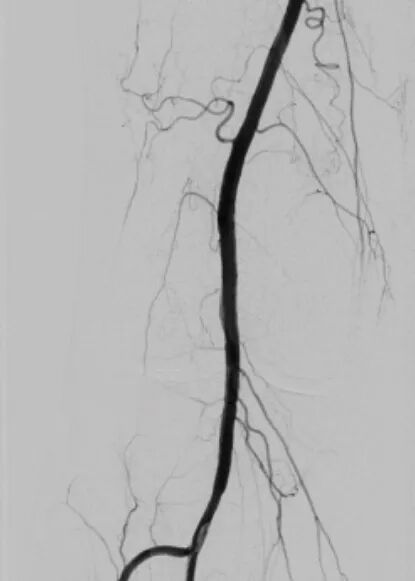

术中抽栓正是基于这一精准诊断,团队迅速调整治疗策略,采用Straub-Rotarex血栓切除系统实施精准抽栓治疗。该系统如同血管内的“吸尘器”,能够将血栓碎屑彻底吸出,无需植入支架。

5术后.jpg

7术后.jpg

术后

术后患者下肢静息痛即刻消失,血管血流恢复通畅。这一治疗既规避了盲目植入支架可能引发的远期再狭窄风险,也真正做到了“因病施治、精准施策”。